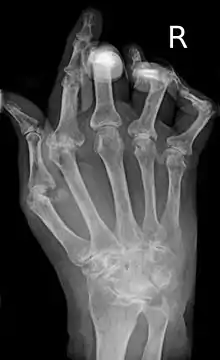

![]() يد متضررة من التهاب المفاصل الروماتويدي يد متضررة من التهاب المفاصل الروماتويدي | |

وتتأثر مفاصل اليد بمعظم أنواع التشوهات. فنجد من المصطلحات الطبية ما يشير إلى هذه الصور المختلفة للتشوهات، مثل "التواء الزند"، " تشوه بوتونيير"، "تشوه رقبة الإوزة"، و"إصبع حرف Z"، لكن هذه الأشكال لم تعد ذات أهمية في التشخيص أو الإعاقة بقدر أهمية العوامل الأخرى.

يمكن ملاحظة تشوه في المفاصل يتمثل بتغير شكل السطوح المفصلية و فقدان التطابق بينها، انعدام للفراغ المفصلي في بعض المفاصل و وجود ما يشبه الالتحام بين عظام الرسغ.

عادة ما تجرى الأشعة السينية X-rays على اليدين والأقدام لمن يعاني من آلام بمفاصل متعددة بالجسم. يمكن آلا يكون هناك أي تغير بالمفاصل بالمراحل الأولى من المرض، ولكن مع تقدم المرض يمكن ملاحظة تآكل، وخلع جزئي بالعظام.